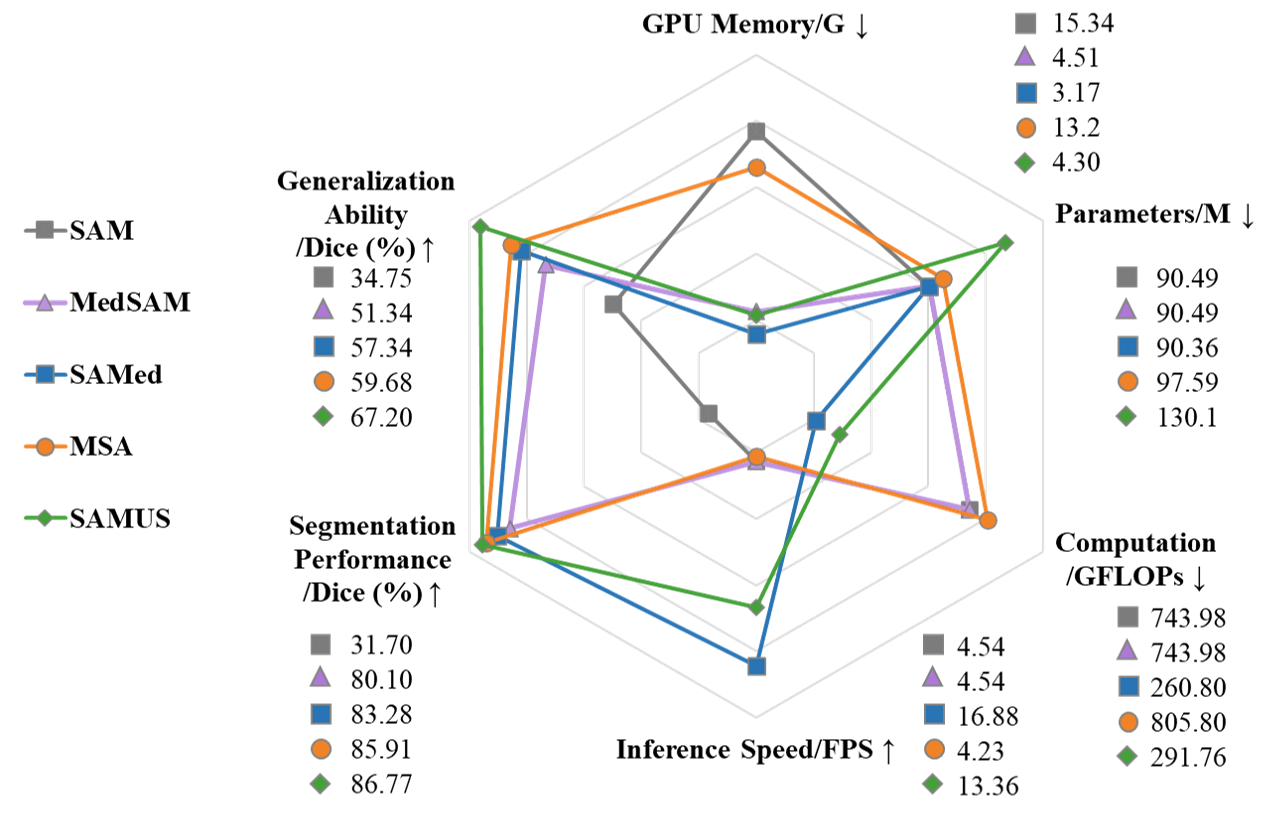

Deployment cost: We conducted a comprehensive evaluation of SAMUS and other foundation models on deployment efficiency, including GPU memory cost, model parameters, computational complexity, inference speed, segmentation performance, and generalization performance. For ease of comparison, the GPU memory is tested when batch size is set as 1 during training and measured by gigabyte (i.e., G). The computational complexity and inference speed are measured by floating-point operations per second (i.e., GFLOPs) and frame per second (i.e., FPS). The segmentation performance is measured by the average Dice score across all seeable datasets and the generalization performance is evaluated based the average Dice score across all unseen datasets. All the above indicators are normalized and depicted with a radar plot as shown in Fig. 7. Among comparison models, SAMed exhibits the lowest GPU memory cost, model parameters, computational complexity, and the fastest inference speed. However, its segmentation and generalization performance is inferior to both MSA and SAMUS. Though SAMUS owns more parameters than other models, its GPU memory cost and computational complexity are the second-fewest and its inference speed is the second-fastest, indicating that SAMUS is a more clinically-friendly model. Moreover, the deployment performance of SAMUS is quite close to that of the most easy-to-deploy method (i.e., SAMed) with much better segmentation and generalization performance.